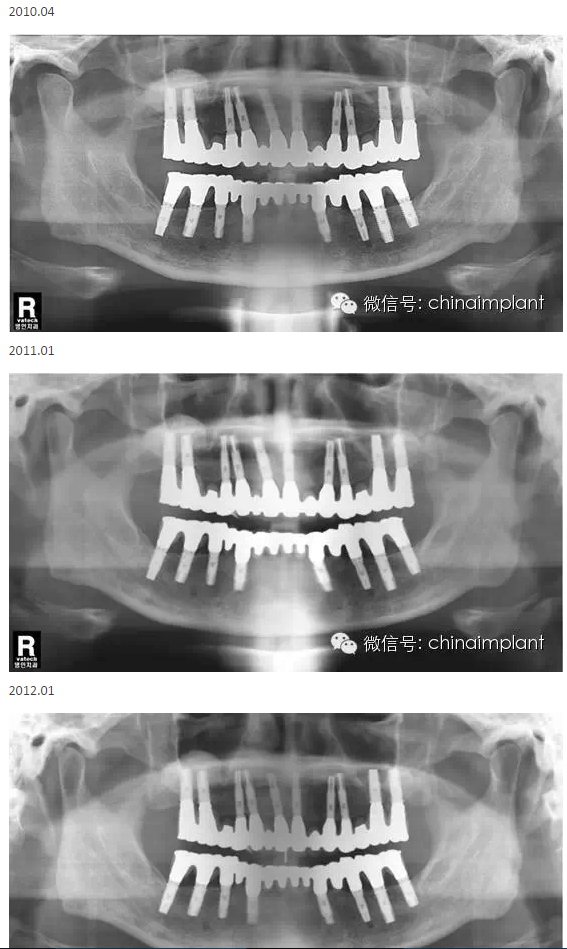

之前針對(duì)全口無(wú)牙進(jìn)行種植修復(fù)的案例中,因?yàn)轭M骨的原因,后期使用橋冠修復(fù)時(shí),一般是3部分(兩側(cè),磨牙,前牙),最近的案例中修復(fù)是一般都是做一體式的橋冠,現(xiàn)在從臨床的修復(fù)案例來(lái)看,沒有什么問(wèn)題。

本案例已經(jīng)將近10年了(2005年12月),但是修復(fù)效果個(gè)人認(rèn)為很不錯(cuò),所以拿出來(lái)和大家分享。

從修復(fù)全景片上看到牙齒排列非常好